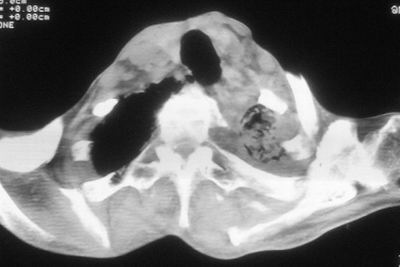

标题: CT11864:男,47岁,反复咳嗽、咯痰、咯血3年,请分析. [打印本页]

患者,男,47岁,反复咳嗽、咯痰、咯血3年,再发5天。痰培养未找到真菌、抗酸杆菌、癌细胞。

左肺上叶体积明显缩小,其内见多发透光区,纵隔向左侧移位,左肺下叶多发班片状病灶,边界模糊,1左肺上叶先天肺发育不全,2左肺下叶肺炎,

左肺上叶结核伴肺纤维化,纵隔移位,左肺下叶感染性病变,建议抗炎抗结核后复查,双肺气肿.

考虑:左肺慢纤伴霉菌球形成、双肺全小叶型肺气肿。

1)考虑为:左肺上叶肺结核(空洞形成),伴左下肺感染;不排除霉菌感染可能。2)肺气肿。

左肺上叶结核伴肺纤维化空洞形成并左肺下叶感染,纵隔牵拉移位,建议作进一步检查排除左侧肺霉菌感染可能。